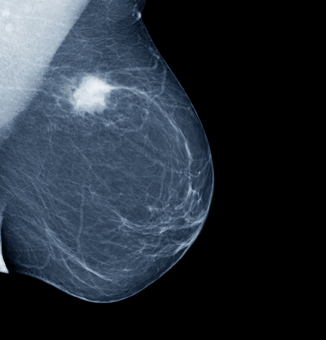

5. I DON’T GET MAMMOGRAMS BECAUSE THEY DON’T HELP

Breast cancer Mammogram_tumorwebThis is another controversial issue that has fuelled endless discussions among experts. Regular mammograms do not prevent or reduce breast cancer. They just detect breast cancer that already exists, but an earlier stage, thus reducing deaths among breast cancer patients by about 17% if done every two years, by 20% if done annually. Other studies have found a 30% reduction in mortality. In addition, since cancers are found earlier, less mastectomies are needed, and most of the women can be treated conservatively (just removing the lump).

These figures mean that thousands of women get to live thanks to mammograms. However, some experts believe that the reduction in mortality mammograms offer is “modest”, which led to intense confusion and disagreement as to whether mammograms are worth doing, and how often they should be done. Mammogram opponents also state that the exam has a considerable false positives rate (that is, it suggests malignancy when something is benign), leading to unneeded breast biopsies, increased health costs and extra anxiety.